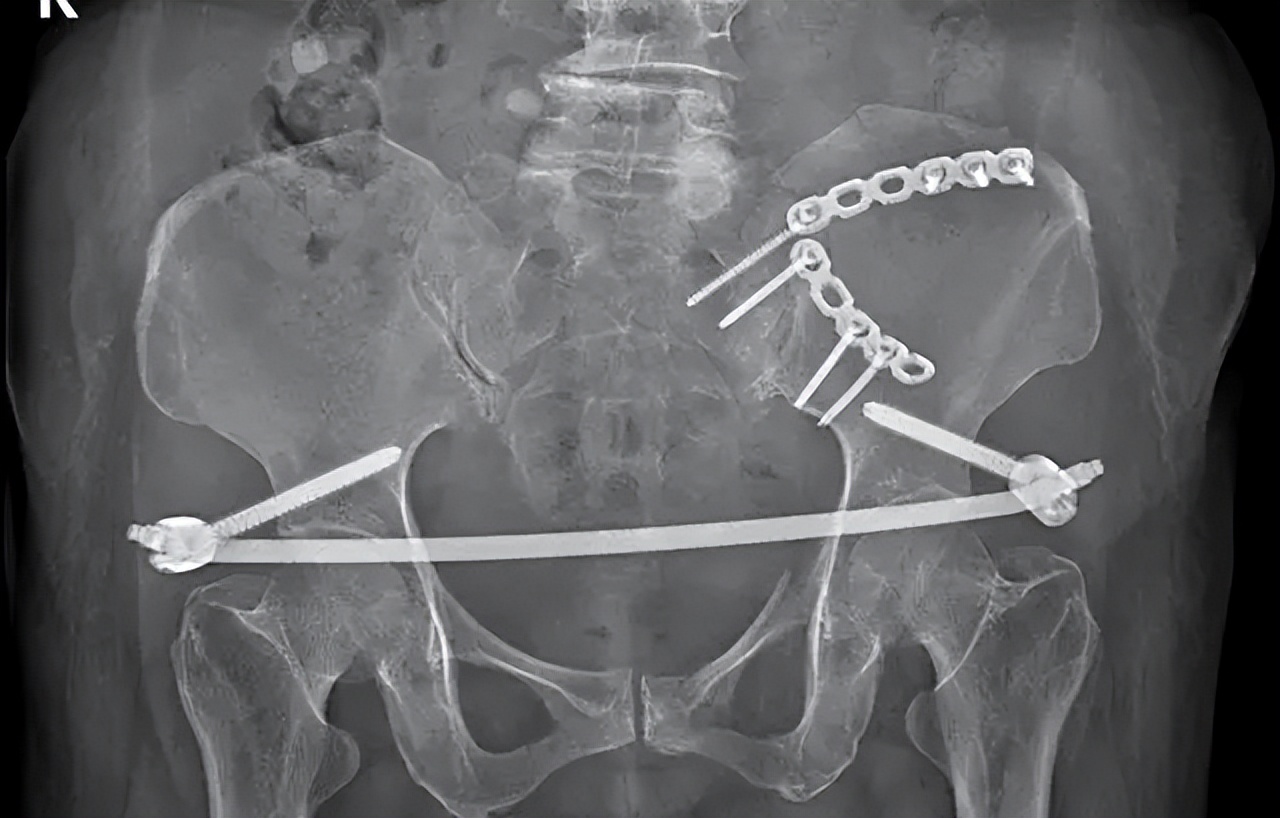

骨盆后环的稳定性可用骶髂关节前方双钢板来维持,前路双钢板固定从提出起便被广泛的认可,一直到现在还在被临床经常实用。

前路双钢板有多种类型可供选择,比如蝶形钢板、三孔或者四孔重建钢板等,但现在最常用的还是三孔或者四孔重建钢板。

前路手术也具有并发症少的优点,并且前路双钢板固定还允许手术固定骨盆后环的同时固定骨盆前环,实现骨盆前后环同时固定优点;

在双钢板固定的过程中,也有许多注意事项,由于骶神经丛的存在,通常骶骨侧钢板只需要置入一枚螺钉即可。

并且前置双钢板之间所呈角度也对稳定性的维持有较大影响, 通常认为前路双钢板之间所呈60-90度时,固定效果最佳,可避免剪切应力的产生,并且整个手术过程是在直视下进行的,可以在直视下看到血管神经。

同时予以保护,极大的减少了医源性损伤的发生,但是此方法手术切口大, 对于患者的损伤严重,术中出血量多,虽然可直视看到血管神经,但是解剖位置深在,损伤血管神经的风险也较大。